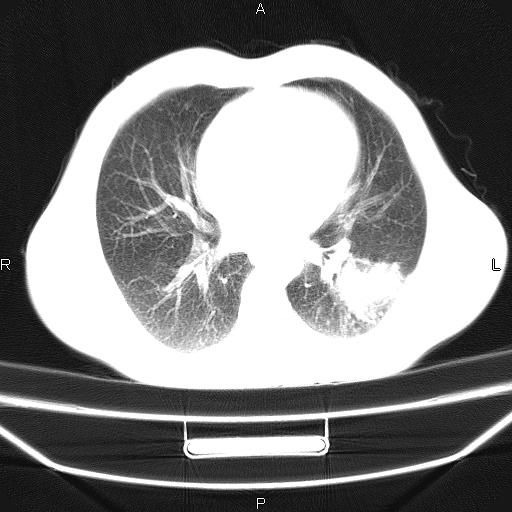

患者,男,40岁。间断发热,咳嗽二十余日。体温最高达38.9° 在当地诊所抗炎治疗三天后体温降至正常,患者自行停药。今又发热。胸片示,左下肺阴影。

左下肺片状高密度影,境界模糊,密度不均,考虑感染性病变可能性大,建议抗炎治疗后复查。左肺门增大,不除外占位性病变,必要时支气管镜检。